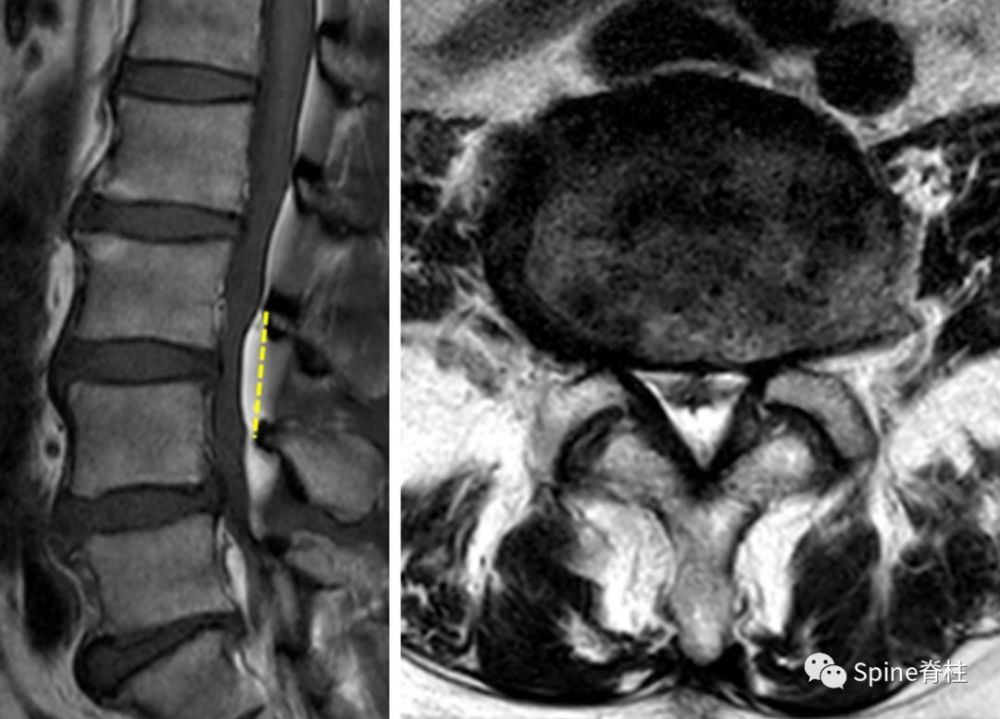

椎管狭窄影像学图片,椎管狭窄的片子图片

术前ct影像提示:椎间盘突出,并椎管狭窄.

骨科精读|mri提示腰椎管狭窄症的几个特殊征象,看这篇就够了_腾讯新闻